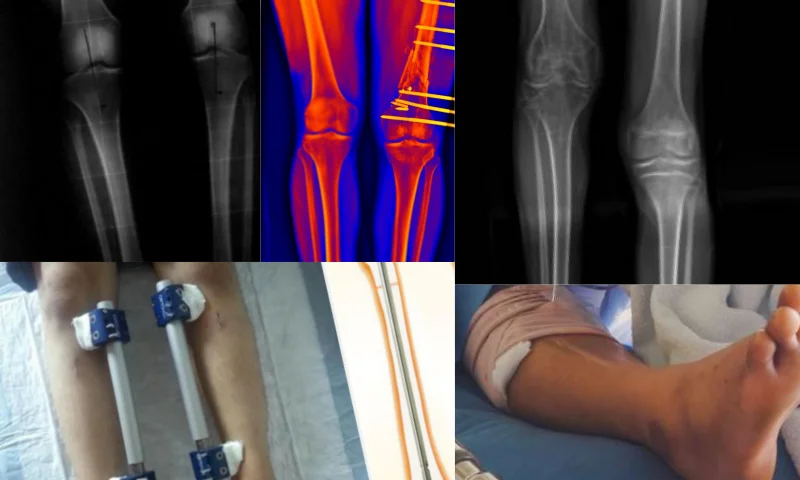

Uzuv Uzatma Cerrahı yöntemi nedir ve hangi alanlarda kullanılır? Yaşına göre yaşıtlarından daha kısa boylu olan ve 1 metreyi geçmeyen kişilere cüce denir. Çocuklarda bazen büyüme kimi zaman 16 yaşına kadar gecikebilir. Ayrıca bu duruma ek olarak diyabet, konjenital kalp hastalığı ve böbrek hastalığı gibi hastalıklarda büyümeyi etkileyebilir. Örneğin Acondroplasic ve hipochondroplasia gibi tanılar cücelik nedenlerini tetikleyen kalıtsal durumlardandır.

Uzuv uzatma cerrahisi gerektiren Hipokondroplazi rahatsızlıkları, acondroplazi kökenlidir ve FGFR3 genindeki bir anormallikten kaynaklanır. Bu hastalığın tanısı anne karnındayken kan testi ile kolayca yapılabilir. Çocuk büyüdükçe akranlarının gerisinde kalır ve iskelet sistemindeki anormallikler gün yüzüne çıkar. Enkondral ossifikasyon bozukluğu ise özellikle büyüme plakalarının orta kısımlarını etkiler. Burada vücut yüksekliği normaldir ayrıca Pelvis ve kafatasının diğer kemikleri de normal gelişim gösterir. Öte yandan rahatsızlık, kolların ve bacakların kısalmasına ve izomelik mikromelik kısalığı olarak bilinen kısa kemiklere yol açar. Erkeklerde maksimum uzunluk 131 cm ve kadınlarda 124 cm' dir. Yüzde alın çıkıntılıdır, elmacık kemikleri ve çene kemiği küçüktür, eller kısa ve geniştir, dirsek eklemi tamamen açılmaz. Bu çocukların zekaları normaldir ayrıca 20' li yaşlarda omurga sorunları ortaya çıkabilir.